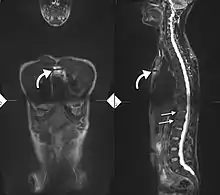

34-year-old male with AS. Inflammatory lesions of the anterior chest wall are shown (curved arrows). Inflammatory changes are seen in the lower thoracic spine and L1 (arrows).

Ankylosing spondylitis is a member of the more broadly defined disease axial spondyloarthritis.[17] Axial spondyloarthritis can be divided into (1) radiographic axial spondyloarthritis (which is a synonym for ankylosing spondylitis) and (2) non-radiographic axial spondyloarthritis (which include less severe forms and early stages of ankylosing spondylitis) [17]

While ankylosing spondylitis can be diagnosed through the description of radiological changes in the sacroiliac joints and spine, there are currently no direct tests (blood or imaging) to unambiguously diagnose early forms of ankylosing spondylitis (non-radiographic axial spondyloarthritis). Diagnosis of non-radiologic axial spondyloarthritis is therefore more difficult and is based on the presence of several typical disease features.[17][18]